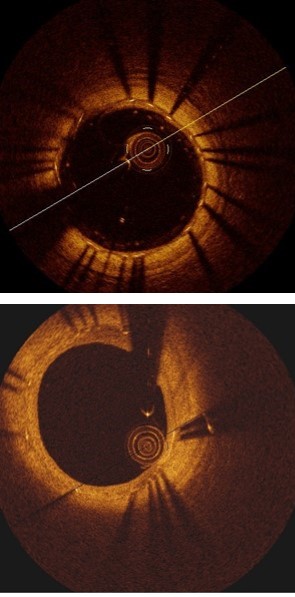

Refer to caption

(a) Image

(b) Label

(c) Locals.

(d) Global.

(e) Ours

Figure 5: Example results of struts detection. Red arrows indicate the detection errors.

Table 1, Fig. 3(b) and Fig. 5 compared the main components of our method individually to quantify their contributions to the final detection results. These results demonstrate that Local-Network has higher recall and we attribute this to the usage of patch-based network to detect all the potential strut candidates. In contrast, Global-Network achieved higher precision for its ability by adding global context, e.g., appearance information, as part of the learning process, which ensures all the detected struts are consistent with the shape of the stent. Table 1, Fig. 3(b) and Fig. 5 also show the advantages from our combination which integrates complementary detection results produced at individual components.